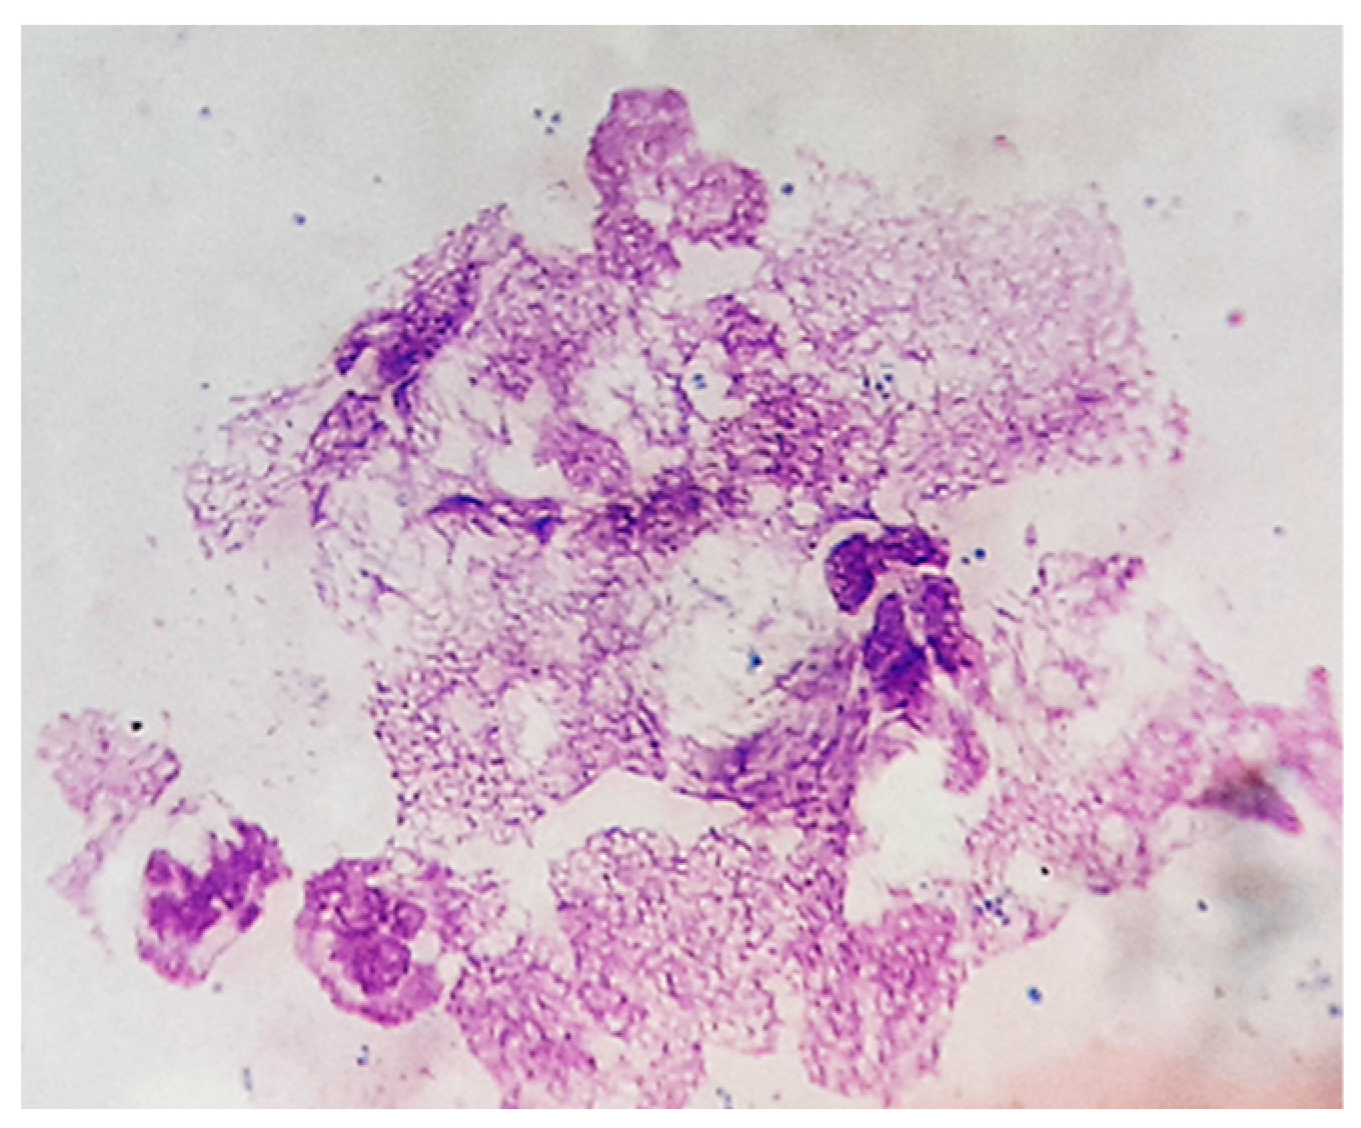

3. Results